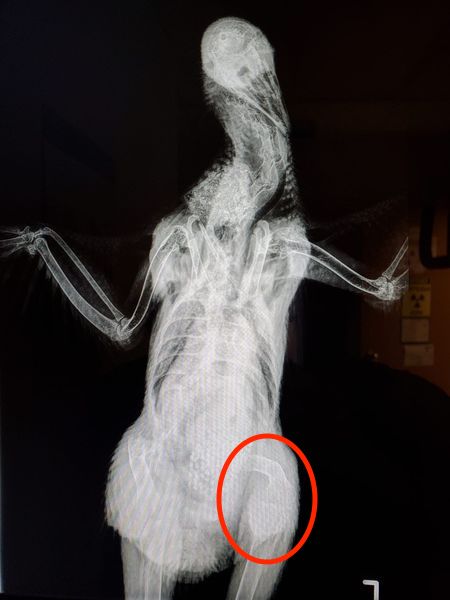

“My 2½ year old Australorp is reluctant to walk, unable to scratch the ground, and has become less social with her flock. The last egg she laid was shell-less about 2 months ago. She eats and poops normally. I am a vet tech and took these x-rays at my clinic but none of the vets I work with know much about chickens. This has been steadily getting worse over the last few months.” – Becky Brooks

Dr Bowes: The femur is obviously badly bowed and is too smooth for it to be a poorly healed fracture. Perhaps the hen had rickets when she was younger or has a metabolic bone disease. The positioning of the x-rays was not ideal (the bad leg is obscured in the last photo) and there was no labeling. It’s possible that there is a pelvic fracture that is not visible, but it’s impossible to assess by looking at the radiographs. The only thing you can offer at this point is pain management.